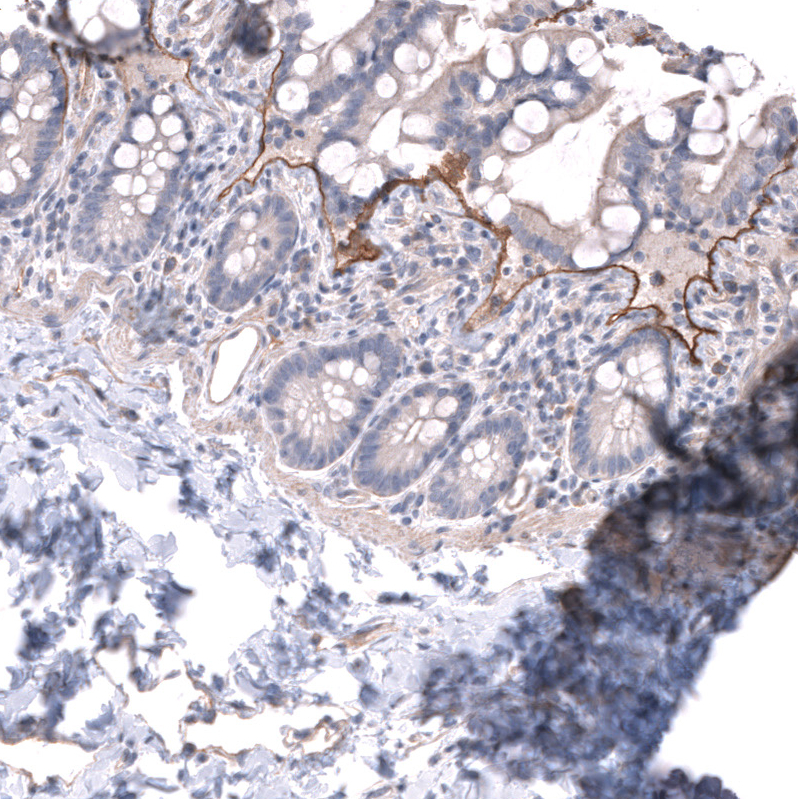

Immunohistochemical staining of human skin shows moderate positivity in basement membrane of epithelial cells.